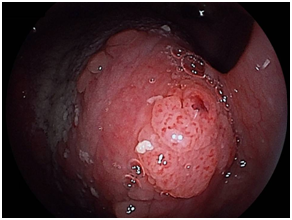

We detected 11 cases of superficial squamous cell carcinoma of the base of the tongue between April 2012 and March 2016. All the patients were complicated with current (n=3) or previous (n=8) esophageal squamous cell carcinoma. The patient characteristics are shown in Table 1. The mean age of the patients was 63.7years (range, 49-73years), and all patients were male. Four cases were diagnosed using trans-nasal endoscopy with the FICE system, seven cases were diagnosed using trans-nasal endoscopy with the LASERIO system. The average time to complete a thorough examination for one patient was approximately from 1 to 2minutes, regardless of the presence of abnormal findings. Biopsy specimen were obtained in all patients, and diagnosed as squamous cell carcinoma pathologically. Table 2 shows the treatment results. Five lesions were flat type (Figure 4A), four were elevated (Figure 4B), and two were depressed (Figure 4C). Regarding the tumor size, eight were T1, three were T2. No lymph node metastasis was detected in any case. Six cases were treated by endoscopic laryngo-pharygeal surgery,15 and 3 cases were treated by chemo-radiotherapy. One case was followed because of esophageal cancer. One case was treated by trans-oral robotic surgery at another hospital. For the seven resected specimens, the median tumor thickness was 800μm (range, 250-3000μm), and the median tumor diameter was 11mm (range, 10-25mm). Histologically, two of these lesions were squamous cell carcinoma in situ, five showed microinvasion of the subepithelial tissue. During a median follow-up period of 26months (range,11-56months), 1 patient, which patient’s tumor thickness was 3000μm, developed lymph node metastasis, which was treated by neck lymphadenectomy and chemo-radiotherapy. Three of the 11 patients cases were died of another disease, and 8 were alive as drafting this manuscript.

Figure 4A Flat type

Macroscopic types of superficial squamous cell carcinoma of the base of the tongue.